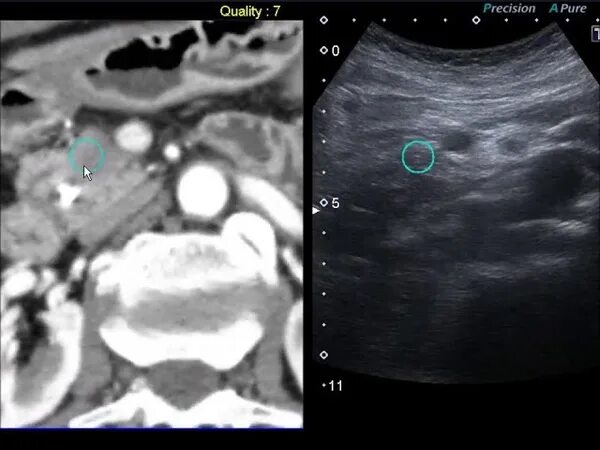

Как делают биопсию поджелудочной